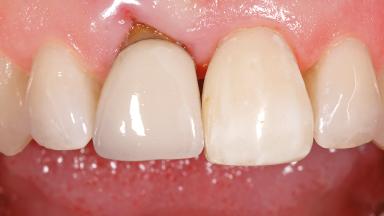

Early Placement of an Implant in a Maxillary Right Central Incisor Site

This 41-year-old female patient was referred to the clinic for the replacement of the right central incisor, since the tooth had developed a root fracture in the long axis that made extraction necessary. The healthy, non-smoking patient was first seen with the tooth still in place. A detailed Esthetic Risk Assessment was performed.The patient was worried about her dental esthetics and had high expectations for a successful treatment outcome from an esthetic point of view. The patient had a medium lip line that displayed parts of the gingiva in the anterior maxilla upon smile.

Abutment Type Customized

Prosthesis Type FDP

Esthetic Risk High

Provisional Implant-Supported Prosthesis Prosthodontic margin < 3 mm apical to mucosal margin Prosthodontic margin < 3 mm apical to mucosal margin